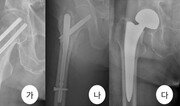

평균수명의 증가로 고령인구가 늘면서 골다공증이나 낙상 관련 골절 환자가 증가하고 있다. 대표적인 것이 고관절에 생기는 골절이다. 특히 고령층에서 고관절 골절이 생기면 근육량 부족으로 거동 능력과 회복력이 떨어져 요양시설에 가게 되는 상황이 흔하게 발생한다. 고관절 골절을 방치할 경우 장기간 침상생활로 인해 욕창, 폐렴, 심장질환 악화, 정맥혈색전증 등 치명적인 합병증이 발생할 수 있다. 고관절 골절은 사망률이 1년 내 25%, 2년 내 70%에 달할 정도로 높다. 수술을 받더라도 1년 내 사망률 14.7%, 2년 내 사망률이 24.3%에 이른다. 젊은 성인은 교통사고나 추락 등 사고로 인한 고관절 골절이 많다. 노인은 전체의 90%가 골다공증으로 뼈가 약해져 있어, 넘어지거나 주저앉는 단순 낙상에도 고관절 골절이 발생할 수 있다. 윤한국 국민건강보험 일산병원 정형외과 교수는 “골절이 발생하면 조기에 회복하는 것이 합병증 및 사망률을 줄일 수 있기 때문에 수술을 우선 고려하는 것이 좋다”며 “수술을 통해 걷는 것이 가능해지면 침상생활로 인해 생기는 합병증을 줄일 수 있다”고 말했다. 고관절 골절을 예방하기 위해서는 비와 눈이 오는 경우 외출을 줄이고, 집안에서는 낙상이 일어나기 쉬운 욕실 등에 미끄럼 방지 시설을 설치하는 것이 좋다. 또 균형감각을 기르거나 근력을 키우는 운동을 하는 것이 좋다. 가벼운 유산소운동도 골절 예방에 도움이 된다. 윤 교수는 “주기적으로 골밀도 검사를 하고 골절 예방에 효과적인 약물을 투여하는 것도 좋다”면서 “평소 보행 장애가 있다면 지팡이, 목발 등 보조기구나 옷처럼 착용하는 고관절 보호대를 착용하는 게 골절 예방에 효과가 있다”고 설명했다.이진한 의학전문기자·의사 likeday@donga.com}